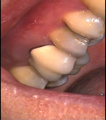

Surgical Endodontic Treatment

Hemisection with Cast Post and Core